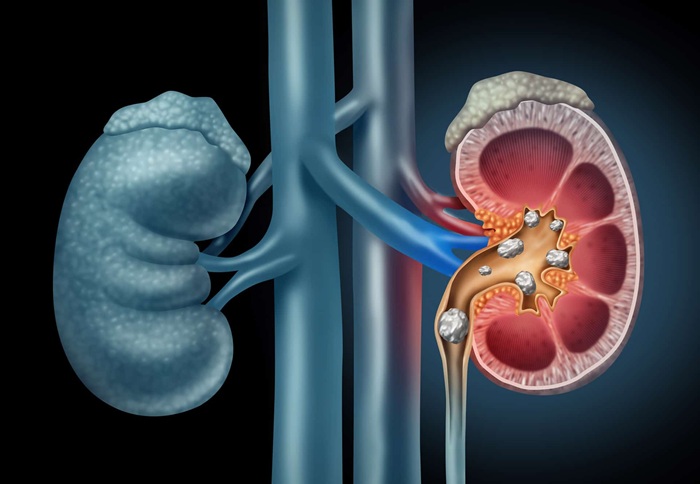

Οι πέτρες στο ουροποιητικό σύστημα εμφανίζονται συνήθως όταν ένας μεγάλος αριθμός αλάτων στα ούρα δημιουργεί συμπλέγματα που δεν αποβάλλονται κανονικά (από τα ούρα) και φράζουν τη δίοδο του ουροποιητικού.

Οι πέτρες στο ουροποιητικό σύστημα εμφανίζονται συνήθως όταν ένας μεγάλος αριθμός αλάτων στα ούρα δημιουργεί συμπλέγματα που δεν αποβάλλονται κανονικά (από τα ούρα) και φράζουν τη δίοδο του ουροποιητικού. Αυτά τα συμπλέγματα αλάτων (πέτρες) σχηματίζονται επειδή ο ασθενής έχει ένα πρόβλημα στην απέκκρισή τους παράλληλα με μια υψηλή διατροφική πρόσληψη.

Οι 4 κύριες μορφές πέτρας είναι οι εξής:

- Πέτρες ασβεστίου

- Πέτρες ουρικού οξέος

- Πέτρες κυστίνης

- Πέτρες στουρβίτη

Πέτρες ασβεστίου

Οι πέτρες που περιέχουν ασβέστιο είναι κυρίως οι πέτρες οξαλικού και φωσφορικού ασβεστίου. Η διατροφή δεν φαίνεται να επηρεάζει την εμφάνιση λίθων φωσφορικού ασβεστίου.

Οι πέτρες οξαλικού ασβεστίου είναι οι πιο συχνά εμφανιζόμενες και παράγονται είτε γιατί οι νεφροί εκκρίνουν πιο πολύ ασβέστιο, είτε γιατί απορροφάται περισσότερο ασβέστιο από τη διατροφή.